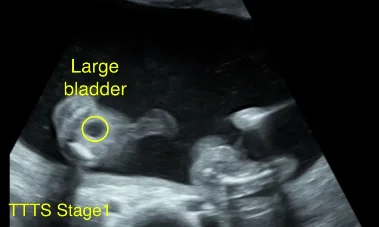

Hội chứng truyền máu song thai (Twin-Twin Transfusion Syndrome - TTTS)